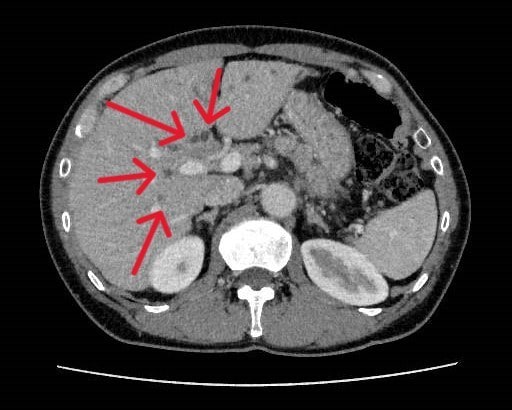

健診にて肝機能異常、皮膚黄染を認め、精査目的で当院消化器内科受診となった。今回実施されたdynamic CTではIgG4関連疾患を疑う所見が認められた。血液検査でもIgG4高値を示しており、IgG4関連硬化性胆管炎と自己免疫性膵炎が疑われ、ステロイドでの加療が開始された。

当該疾患の診断における造影CTの役割